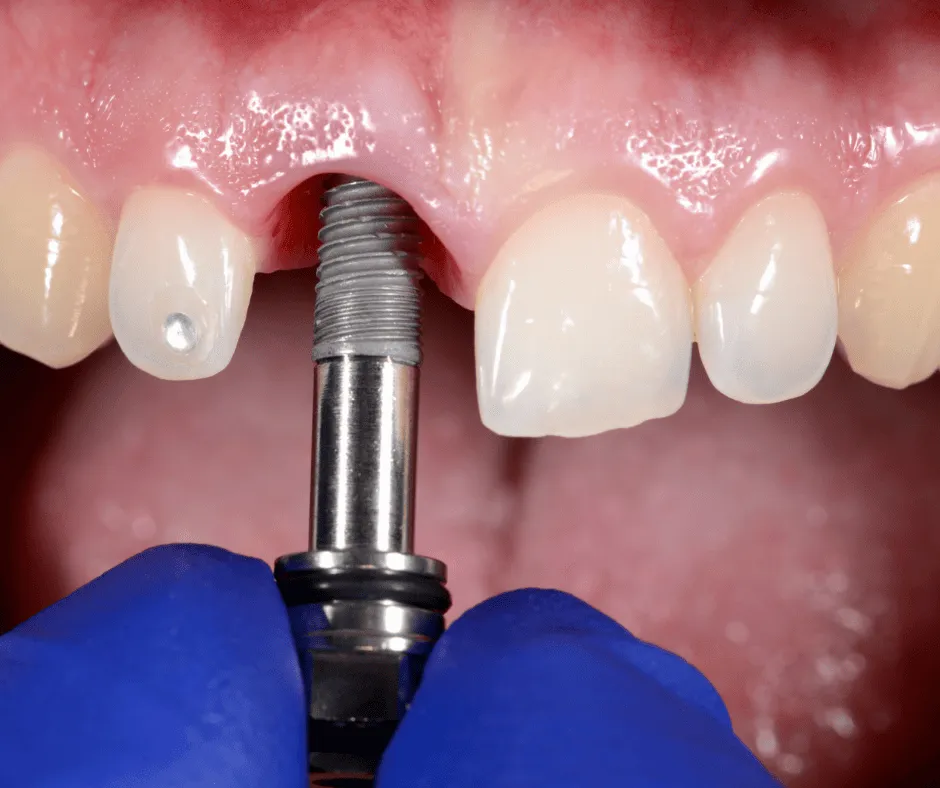

Implantes dentales

colocación quirúrgica de implantes dentales.